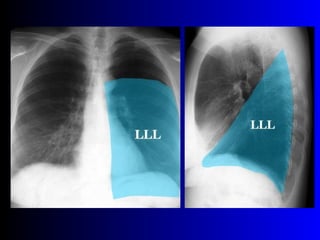

Este documento describe la técnica para realizar una telerradiografía de tórax normal e identifica las estructuras visibles en la imagen, incluyendo los huesos, vasos sanguíneos, grasa, tejido subcutáneo, pulmones y mediastino. Explica que es importante centrar la imagen en los ápices pulmonares, senos costodiafragmáticos e inspiración profunda para una visión clara de las estructuras.